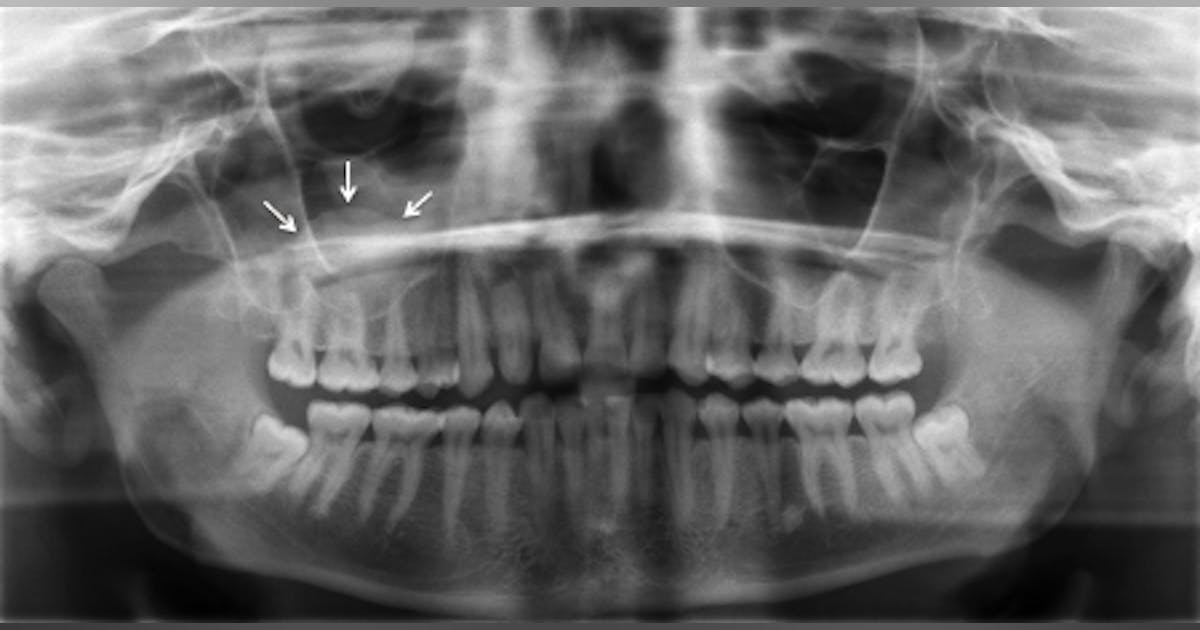

Imaging that allows the dentist to view the entire dentition and related structures on a single image.

Panoramic

Maxillary Sinus

Mandibular Condyle

Mandibular canal/nerve